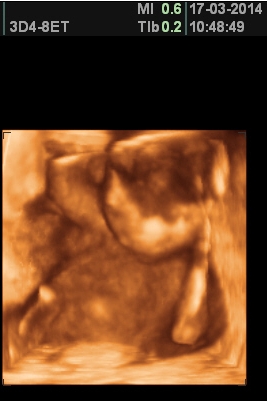

[550892] Káťo fajné fotečky, jaká pohodička...;-)